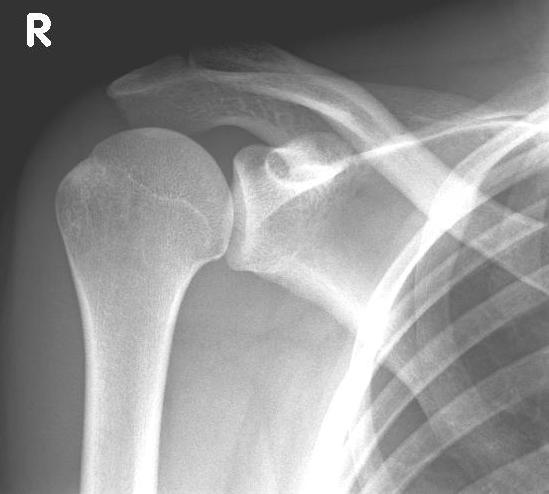

Abbildung2Abbildung1

left: X-ray image of an omarthrosis

right: X-ray of a healthy shoulder joint